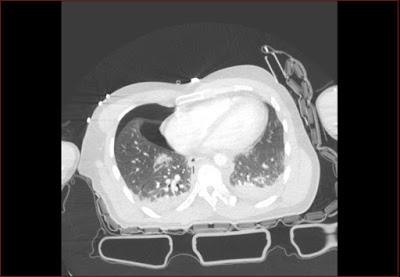

Csigolyatores a thoracalis gerincszakaszon Szerző: admin | jún 10, 2010 | Fracture, Pneumothorax, Trauma | Nincsenek hozzászólások A csigolyatest felso zarolemezt is erinto elulso torese tores a processus spinosuson